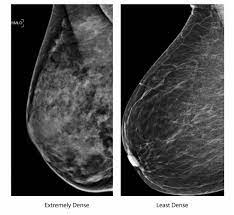

Mammography Wikipedia from upload.wikimedia.org Even if you have a lump in only one breast, pictures will be taken of both breasts. However, in rare cases, breast cancer can be the cause of gynecomastia so, a full mammographic investigation is always necessary. Dense breast tissue appears solid. 1 the gray areas correspond to normal fatty tissue, while the white areas are normal breast tissue with ducts and lobes. This overlapping tissue can cause the resulting image to look like cancer. After a mammogram that didn't show anything, and a sonogram that found the lump, i was diagnosed with stage 2 breast cancer. This is why you should always talk to your doctor if you notice an unexplained change in the size of a breast. We'll show you breast cancer pictures to help you identify any physical traits of the condition.

Essentially, mammograms turn a 3d object into a 2d object. This is why you should always talk to your doctor if you notice an unexplained change in the size of a breast. What does the doctor look for on a mammogram? cancer.org. A screening mammogram is performed at regular intervals to check for breast cancer in women who have no signs or symptoms of the disease. Bright spots on a mammogram that look like potential tumors could turn out to be overlapping tissues or a blood vessel folding over on itself, friedewald said. To license this video for patient education or content marketing, visit: What does breast cancer look like? This overlapping tissue can cause the resulting image to look like cancer. Finding breast lumps and seeing change in the size and shape. Screening mammograms have been used since the 1980s. Digital breast tomosynthesis (tomo), also known as 3d mammography, is a revolutionary new screening and diagnostic breast imaging tool to improve the early detection of breast cancer. Ultrasound characterization of breast masses. indian journal of radiology and imaging. Calcifications are calcium deposits within the breast tissue and they look like small white spots.

Moose & doc breast cancer, 21 may 2018. We'll show you breast cancer pictures to help you identify any physical traits of the condition. Normal breast tissue can look 100,000 different ways on a mammogram. Finding breast lumps and seeing change in the size and shape. Dense breast tissue appears solid. Essentially, mammograms turn a 3d object into a 2d object. American cancer society, 9 oct 2017. That makes it easy to detect abnormalities, which generally show up as white. A 3d mammogram is used to look for breast cancer in people who have no signs or symptoms. More importantly, the overlap can obscure small breast cancers. A screening mammogram is performed at regular intervals to check for breast cancer in women who have no signs or symptoms of the disease. Several patterns of calcifications are seen with dcis, including: Breast cancer and some noncancerous (benign) breast conditions can appear white on a mammogram.

Breast cancer and some noncancerous (benign) breast conditions can appear white on a mammogram. This overlapping tissue can cause the resulting image to look like cancer. Diagnostic mammograms involve taking more views than screening mammograms. It's so important to listen to the messages our bodies are telling. A number of studies have found that 3d mammograms find more cancers than traditional 2d mammograms and also reduce the number of false positives. Ultrasound characterization of breast masses. indian journal of radiology and imaging. Even if you have a lump in only one breast, pictures will be taken of both breasts. Finding breast lumps and seeing change in the size and shape. 1 the gray areas correspond to normal fatty tissue, while the white areas are normal breast tissue with ducts and lobes. A false positive is when a mammogram shows an abnormal area that looks like a cancer but turns out to be normal. Breast cancer can appear as a spiculated mass, cluster of tiny calcifications, smoothly marginated mass, area of subtle distortion or be invisible on. Macrocalcifications, which look like small white dots on a mammogram. One advantage of ultrasound technology is that it allows substantial freedom in obtaining breast images from any orientation.